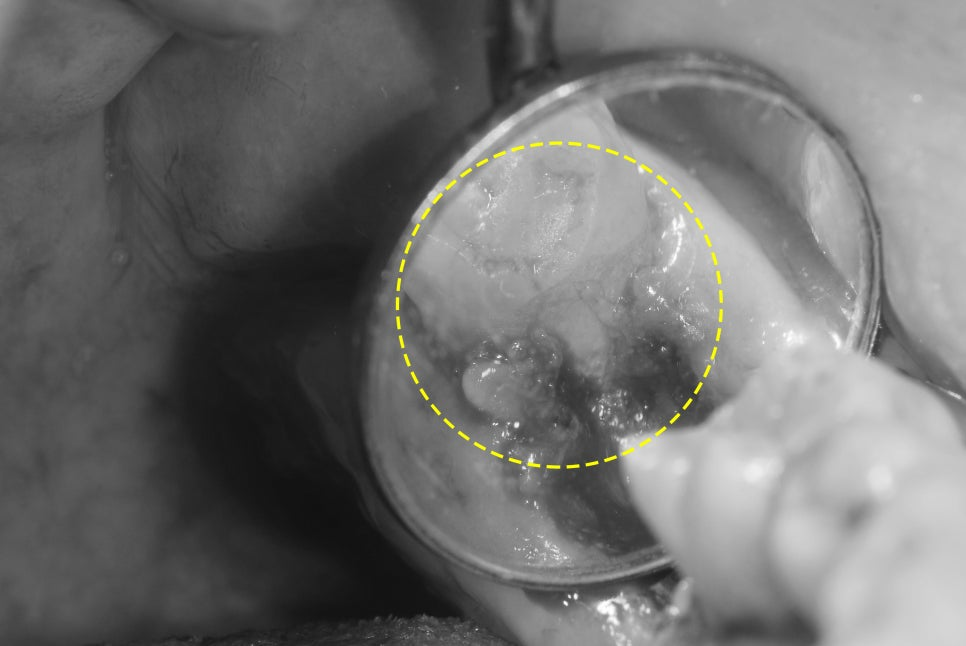

안녕하세요. 박현준 원장입니다. 제가 3년전에 적었던 글을 하나 보여드릴게요. (최근에 치료가 끝났거든요!) 이전 글의 내용을 정리하면 순서로 설명을 드렸었습니다.